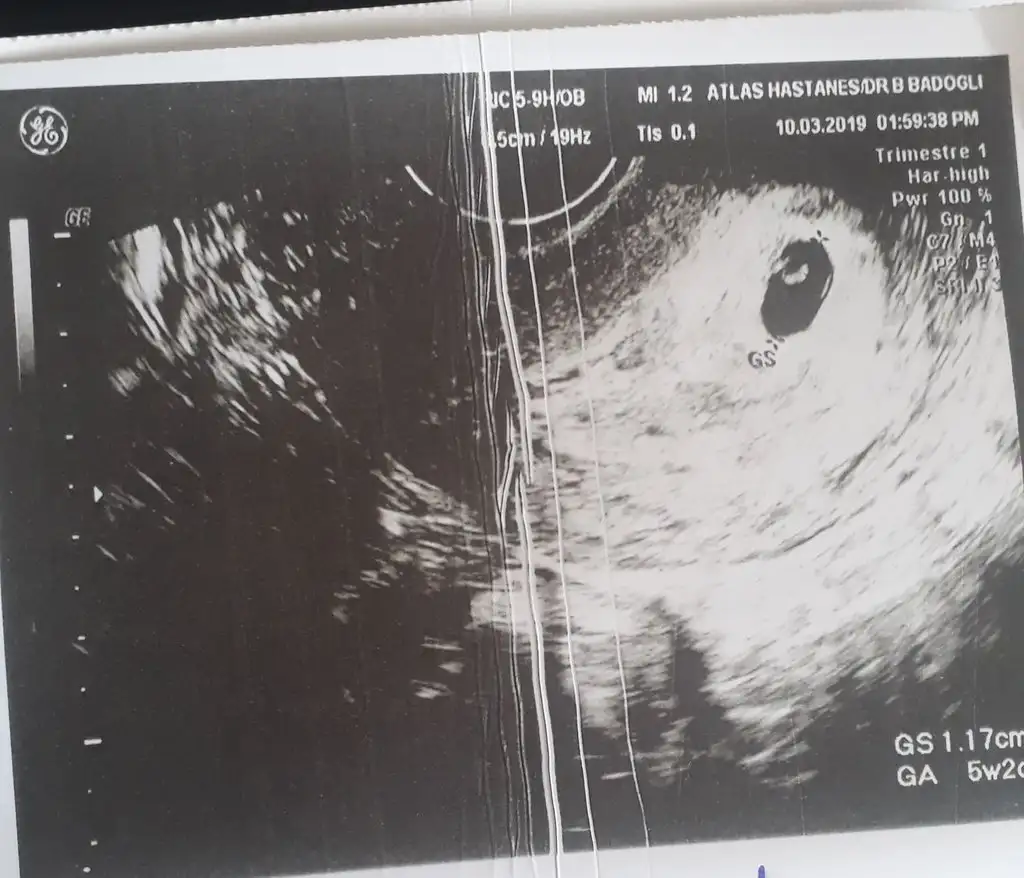

Teşekkürler nokta gibi gözüken karartı kısmetse bebişimizMaşallah ya ultrason kağıdınız varsa bizimle paylaşır mısınız merak ettim

Teşekkürler nokta gibi gözüken karartı kısmetse bebişimiz![]()

bence o yumurta falan değil bebek kesenin içinde yumurta niye olsun ya hu? ümraniyedeki atlas hastanesi mi bu canım ?Anneem yaa maşallaah sahiden içinde birşey gözüküyorrEki Görüntüle 2245459 Bak Bu benimki Sat 26 Ocak ama ultrasında 5+2 gözüktü içini göremiyorum dedi doktor ama içinde birşey var dedim yumurta o dedi

bence o yumurta falan değil bebek kesenin içinde yumurta niye olsun ya hu? ümraniyedeki atlas hastanesi mi bu canım ?

MaşallahAnneem yaa maşallaah sahiden içinde birşey gözüküyorrEki Görüntüle 2245459 Bak Bu benimki Sat 26 Ocak ama ultrasında 5+2 gözüktü içini göremiyorum dedi doktor ama içinde birşey var dedim yumurta o dedi

Bence bebekBu görünen şey ne ki

Bence bebekama dediğim gibi dr.garanti olsun diye bişey dememiştir

Yumurta falan olması imkansız ☺